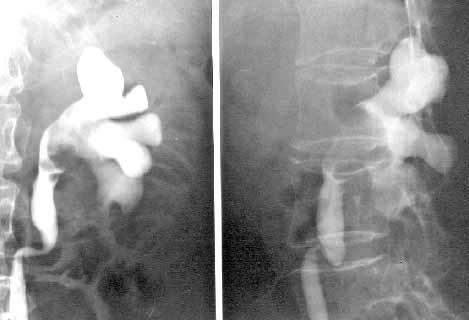

肾盂癌